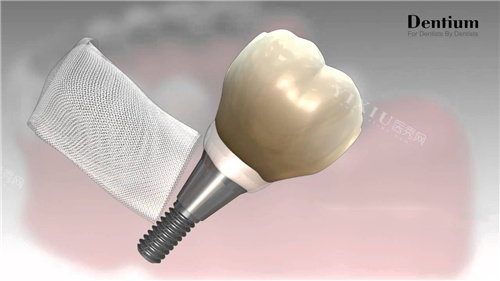

常听医生说“种植体是种植牙的‘根’”,这“根”的好坏,材料和工艺是关键。 德国种植体(如ICX、BEGO、HT)多用医用四级冷作钛,这种钛金属纯度更高(含钛量超99%),表面处理技术更成熟,比如SLA大颗粒喷砂酸蚀技术,能在植体表面形成50-100微米的粗糙结构。用医生的话说:“就像给树根裹了层‘粗糙外衣’,能更快和牙槽骨‘长’在一起。”

韩国种植体(如奥齿泰、登腾、DIO)则多采用高强度钛合金,生物相容性也不错,但钛纯度稍低(约98%)。表面处理技术以微螺纹或纳米涂层为主,虽然结合速度比德国慢点,但胜在成本可控,适合对“快”要求不高的患者。

牙槽骨条件差(比如骨量不足、骨质疏松):德国植体表面粗糙,能加速骨结合,降低“种不活”风险。 缺牙位置在磨牙区(承担咬合力大):德国植体强度更高(抗压值超500MPa),长期用更稳。 对“一劳永逸”有执念:德国品牌临床数据显示,10年留存率超95%(韩国约90%)。